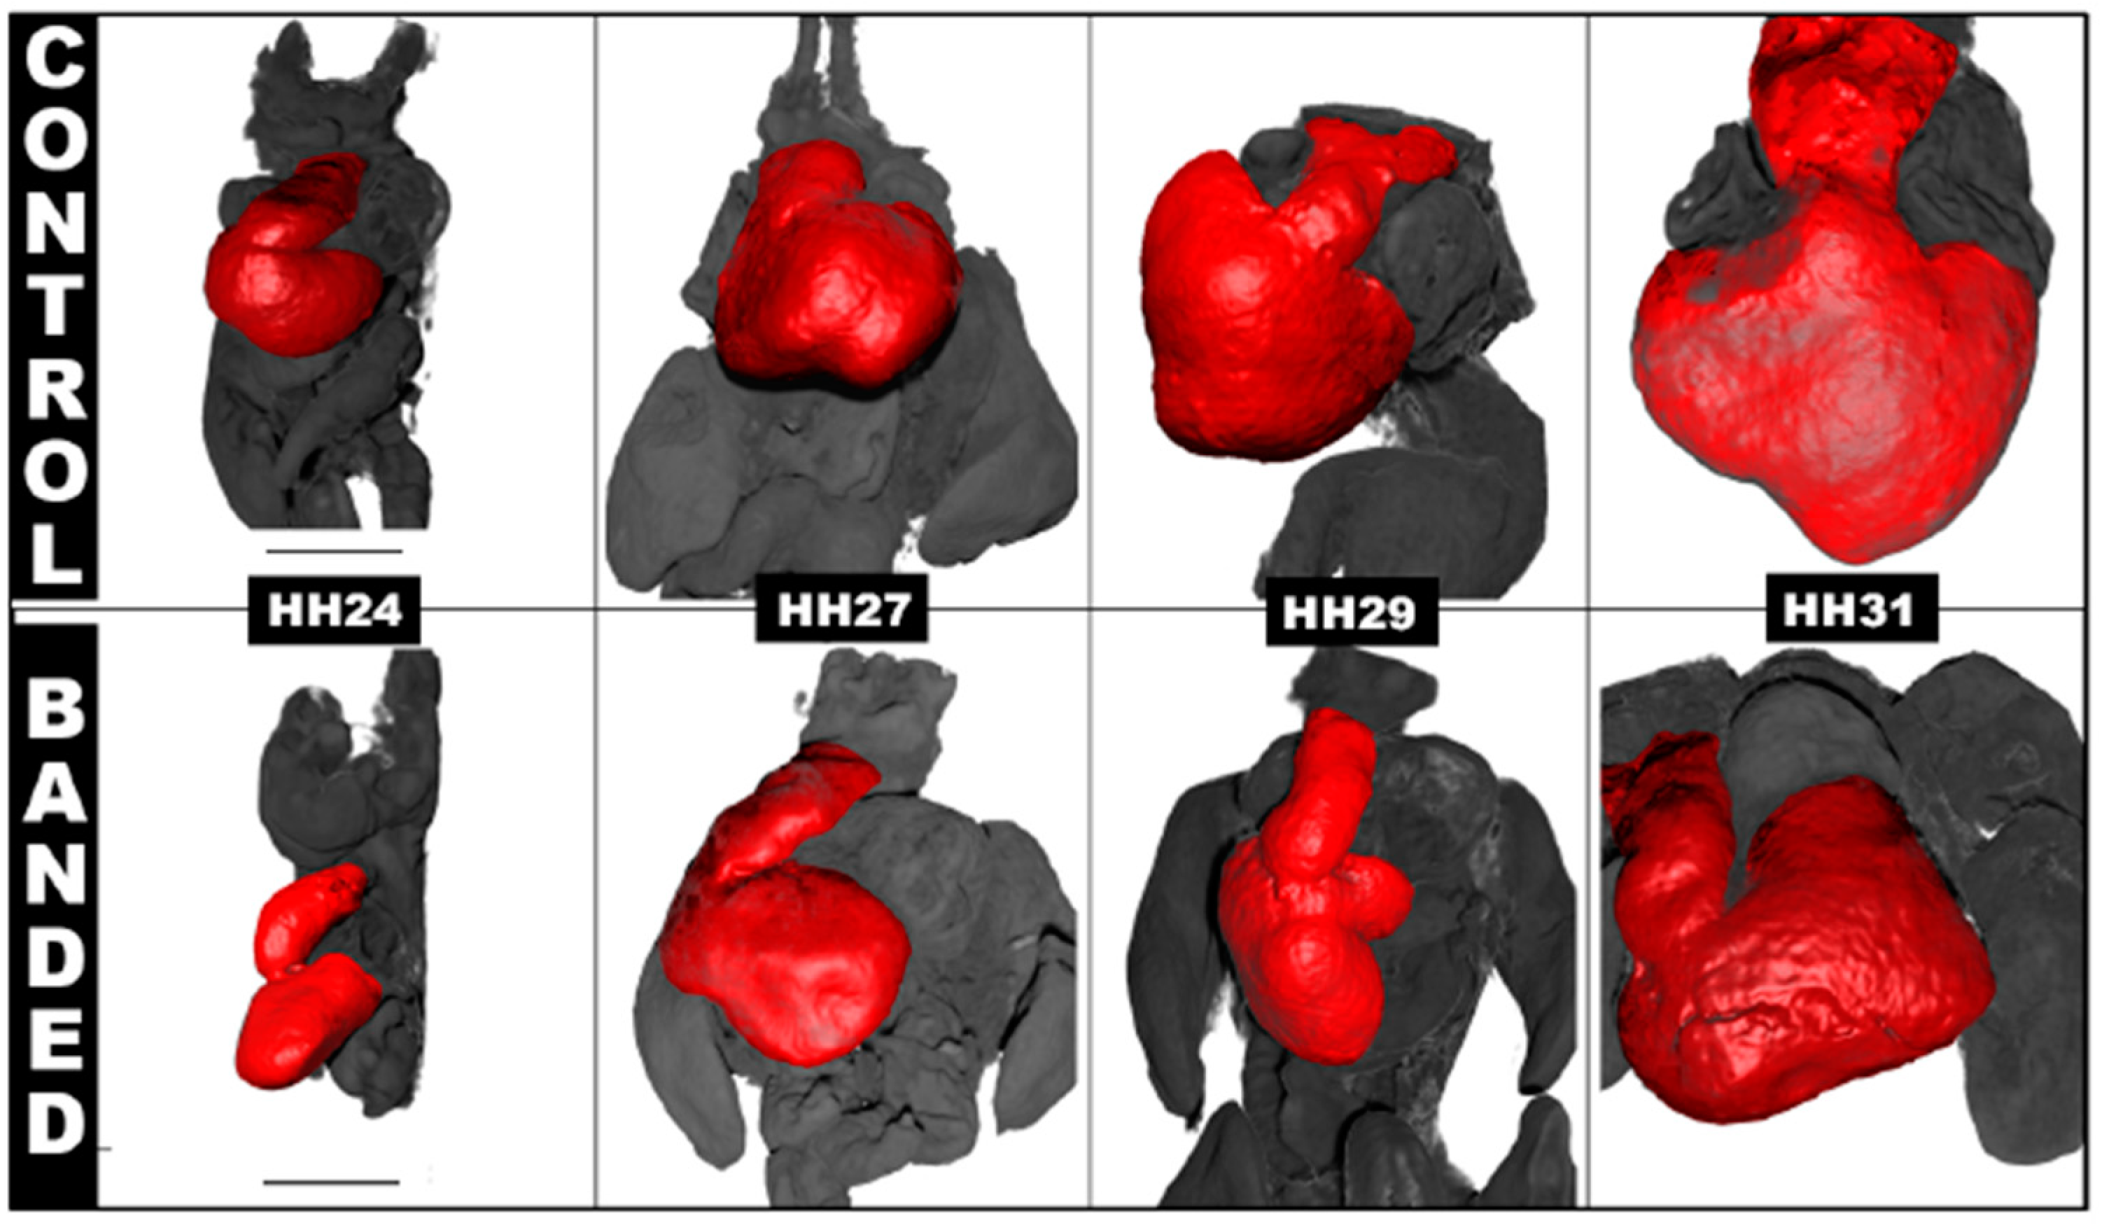

4.2. Hemodynamic Interventions in Avian Models

5.2. Ventricular Formation

5.3. Outflow Tract and Great Vessels